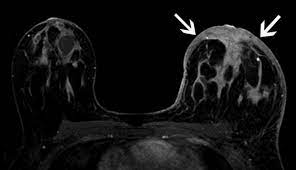

When the cancer grows into the rest of the body through the blood vessels and lymph vessels, breast cancer spreads. Inflammatory breast cancer occurs when cancer cells block the lymphatic vessels in skin covering the breast, causing the characteristic red, swollen appearance of the breast. Inflammatory breast cancer inflammatory breast cancer is a rare type of breast cancer that develops rapidly, making the affected breast red, swollen and tender. A breast mri usually is performed after you have a. The usual cause of inflammatory breast symptoms is breast mastitis or duct ectasia.

The features of a malignant breast condition on mri scan are often to do with the outer irregular borders of a lesion. Inflammatory breast cancer affects breast tissue and can appear unusually dimpled or thick. Absence of lump or breast mass in a patient suffering from an inflammatory skin condition of the breast, suggests the presence of skin or subcutaneous inflammatory condition caused by either infection or inflammatory breast cancer. The skin looks like the skin of an orange, and may be discolored with painful and itchy breast. The breast is enlarged (often of relatively short onset), indurated, erythematous, warm, and may be tender and painful. But not every woman who has been diagnosed with breast cancer needs a breast mri. What does breast cancer look like on a mammogram? A lump in the breast. Breast mri is sometimes used in women who already have been diagnosed with breast cancer, to help measure the size of the cancer, look for other tumors in the breast, and to check for tumors in the opposite breast. Most cases are invasive ductal carcinomas, which develop in the cells lining the milk ducts and spread throughout the breast. The breast can also be painful in inflammatory breast cancer, but this is not always the case. Evaluating the impact of preoperative breast magnetic resonance imaging on the surgical management of newly diagnosed breast cancers. When the cancer grows into the rest of the body through the blood vessels and lymph vessels, breast cancer spreads.

Inflammatory breast cancer is an an aggressive and fast growing breast cancer in which cancer cells infiltrate the skin and lymph vessels of the breast. They're often easy to move around (mobile) and may be tender. Ibc symptoms are caused by cancer cells blocking lymph vessels in the skin causing the breast to look inflamed. symptoms include breast swelling, purple or red color of the skin, and dimpling or thickening of the skin of the breast so that it may look and feel like an orange peel. Unlike traditional forms of breast cancer, inflammatory breast cancers do not develop unusual lumps within the affected breast. The skin is thickened and edematous, classically with a peau d'orange appearance. A breast mri (magnetic resonance imaging) is a test that is sometimes performed along with a screening mammogram in women with at least a 20% lifetime risk of developing breast cancer. What does breast cancer look like on a mammogram? Mri of breast can help breast cancer diagnosis. Inflammatory breast cancer inflammatory breast cancer is a rare type of breast cancer that develops rapidly, making the affected breast red, swollen and tender. A rash isn't the only visual symptom of inflammatory breast cancer. Inflammatory breast cancer (ibc) is rare, making up about 2 to 4 percent of breast cancer cases. Inflammatory breast cancer pictures and symptoms The skin looks like the skin of an orange, and may be discolored with painful and itchy breast.

The Radiology Assistant Mri Of The Breast from radiologyassistant.nl Inflammatory breast cancer pictures and symptoms The breast can also be painful in inflammatory breast cancer, but this is not always the case. The skin of the breast may also appear pink, reddish purple, or bruised. Ridges or thickening of the skin of the breast. Inflammatory breast cancer (ibc) is rare, making up about 2 to 4 percent of breast cancer cases. Need to have physical exam, mammogram, and ultrasound as needed. Sometimes it can be difficult to tell the difference between mastitis and inflammatory breast cancer. Absence of lump or breast mass in a patient suffering from an inflammatory skin condition of the breast, suggests the presence of skin or subcutaneous inflammatory condition caused by either infection or inflammatory breast cancer.

It blocks the lymph vessels in the skin of your breast. They're often easy to move around (mobile) and may be tender. When the cancer grows into the rest of the body through the blood vessels and lymph vessels, breast cancer spreads. Breast lesions and chest wall abnormalities 8. Pitting, thickening, or dimpling of skin on the breast, so that it looks like an orange peel, a condition called peau d'orange. Most cases are invasive ductal carcinomas, which develop in the cells lining the milk ducts and spread throughout the breast. To help determine the extent of breast cancer: There may or may not be an underlying palpable mass. Mri of breast can help breast cancer diagnosis. Inflammatory breast cancer pictures show a red and/or swollen breast that appears inflamed. A breast mri usually is performed after you have a. J natl compr canc netw. If these tests don't answer the quest.